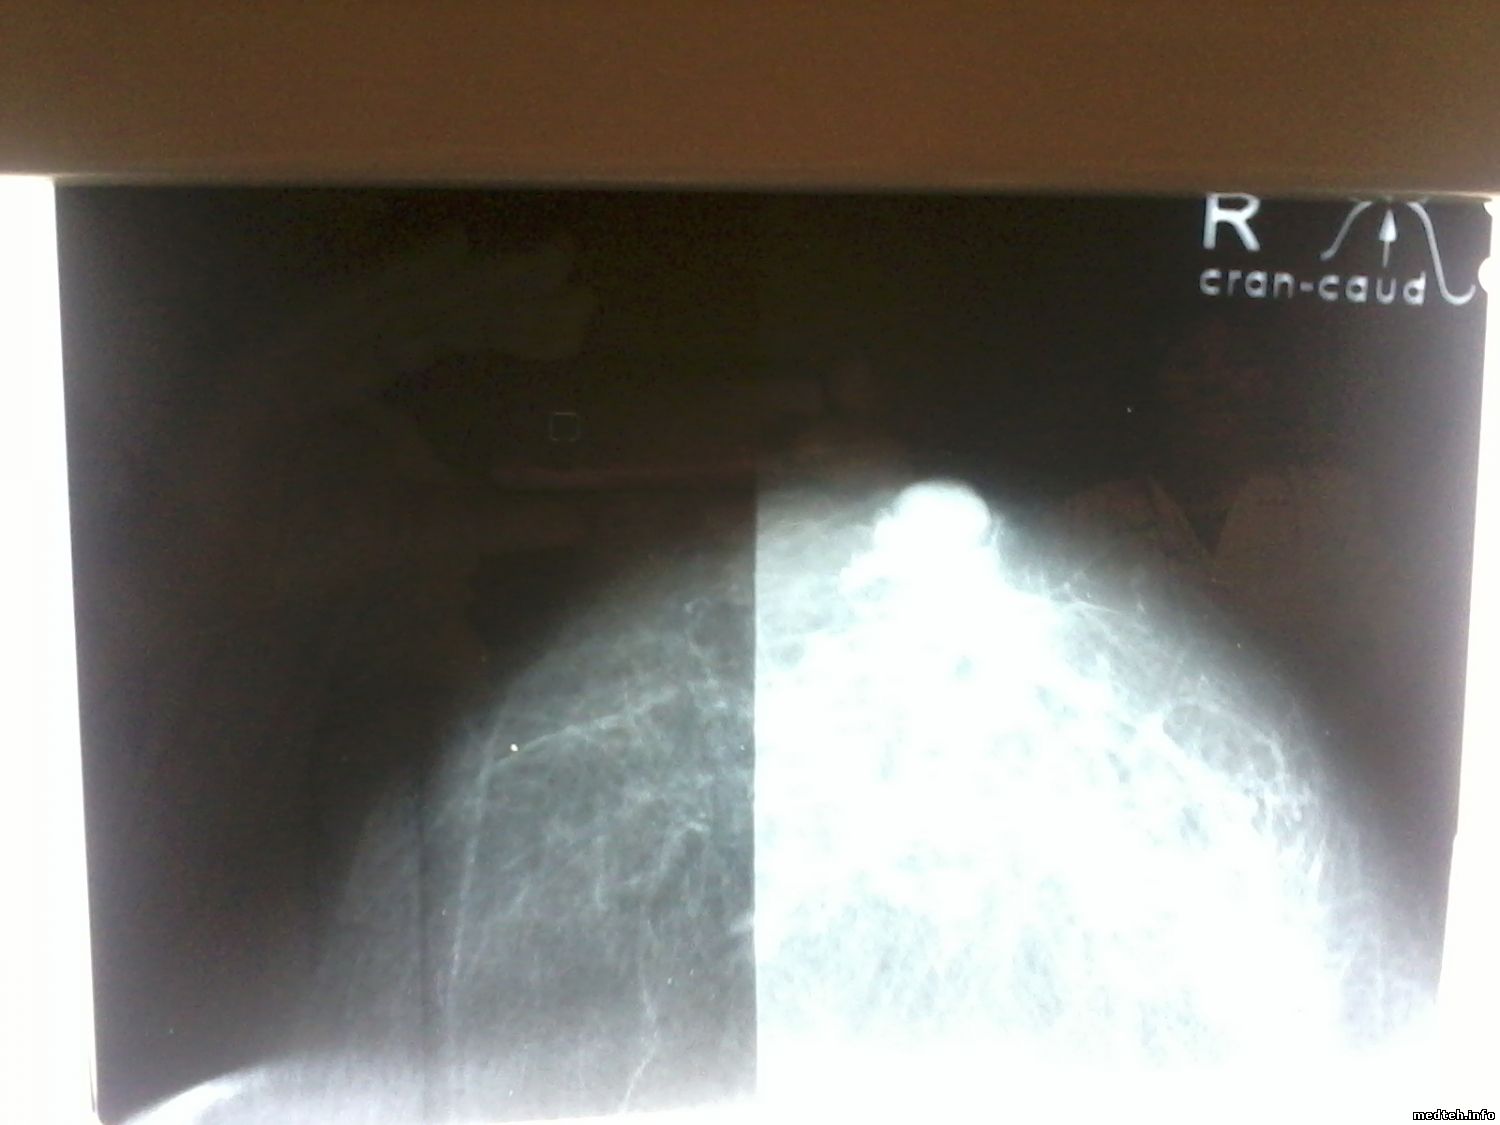

периодически получаются снимки с затемнением ровно пополам. причём в основном на прямых проекциях. кассеты отпадают, осмотрел и на разных бывает. решётка двигается, никаких посторонних предметов нет. сменных фильтров нет( окно видно) Единственный движущийся элемент, зеркало, убирается в другой плоскости. Дефект плёнки отпадает, брали из разных коробок.

фото снимка прилагаю. Кто нибудь встречал подобное?

4633811.jpg (94.0 Kb) · 8354803.jpg (77.1 Kb)

Проявочная машина отпадает, так как вместе с маммографом в той-же машине проявляются снимки с R-графии. нареканий нет. И если сложить снимки сделанные в разные дни один на один, дефект как под копирку........совпадает до милиметра......

Это скорее дефект моего фотоаппарата. снимал снимок на негатоскопе, .

И если сложить снимки сделанные в разные дни один на один, дефект как под копирку........совпадает до милиметра......

Поскольку чудес в природе не бывает, то вычислять дефект придется по цепочке:

- кассеты (усиливающие экраны)

- столик

- фильтр в поле луча

Всё проверять собственными руками и глазами, не доверяя теории и здравому смыслу.